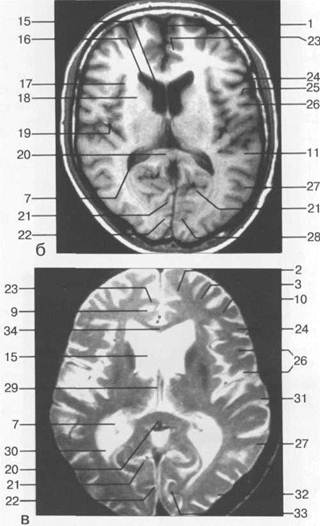

Рис. 1.17. Уровень верхних отделов боковых

желудочков:

а — аксиальный срез КТ;

б — аксиальный срез МРТ (Т1-ВИ);

1 — серп; 2 — верхняя лобная извилина; 3 — средняя лобная извилина; 4 — передняя мозговая артерия; 5 — латеральная щель; 6 — таламус; 7 — треугольник бокового желудочка; 8 — червь; 9 — поясная бороз­да; 10 — нижняя лобная извилина; 11 — верхняя височная извилина; 12 — шишковидная железа; 13 — цистерна четверохолмия; 14 — прямой синус; 15—лобный рог; 16 —головка хвостатого ядра; 17 —перед­ний отдел латеральной щели; 18 — внутренняя капсула; 19 — боковой отдел латеральной щели; 20 — ва­лик мозолистого тела; 21 — теменно-затылочная борозда; 22 — шпорная борозда; 23 — поясная извили­на; 24 — предцентральная извилина; 25 — центральная борозда; 26 — постцентральная извилина; 27— средняя височная извилина; 28 — затылочная доля; 29 — внутренняя вена мозга; 30 — затылочный рог; 31 — поперечная височная извилина (извилина Гешле); 32 — наружная затылочная извилина; 33 — шпор­ная извилина; 34 — мозолистое тело.